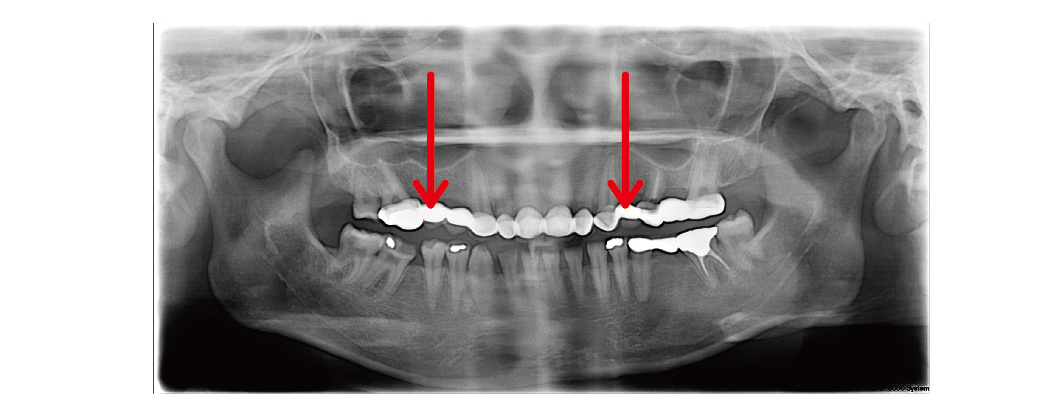

▲初診的環口式X光片檢查,可以看到上顎為長牙橋,容易有清潔死角造成牙齒發炎